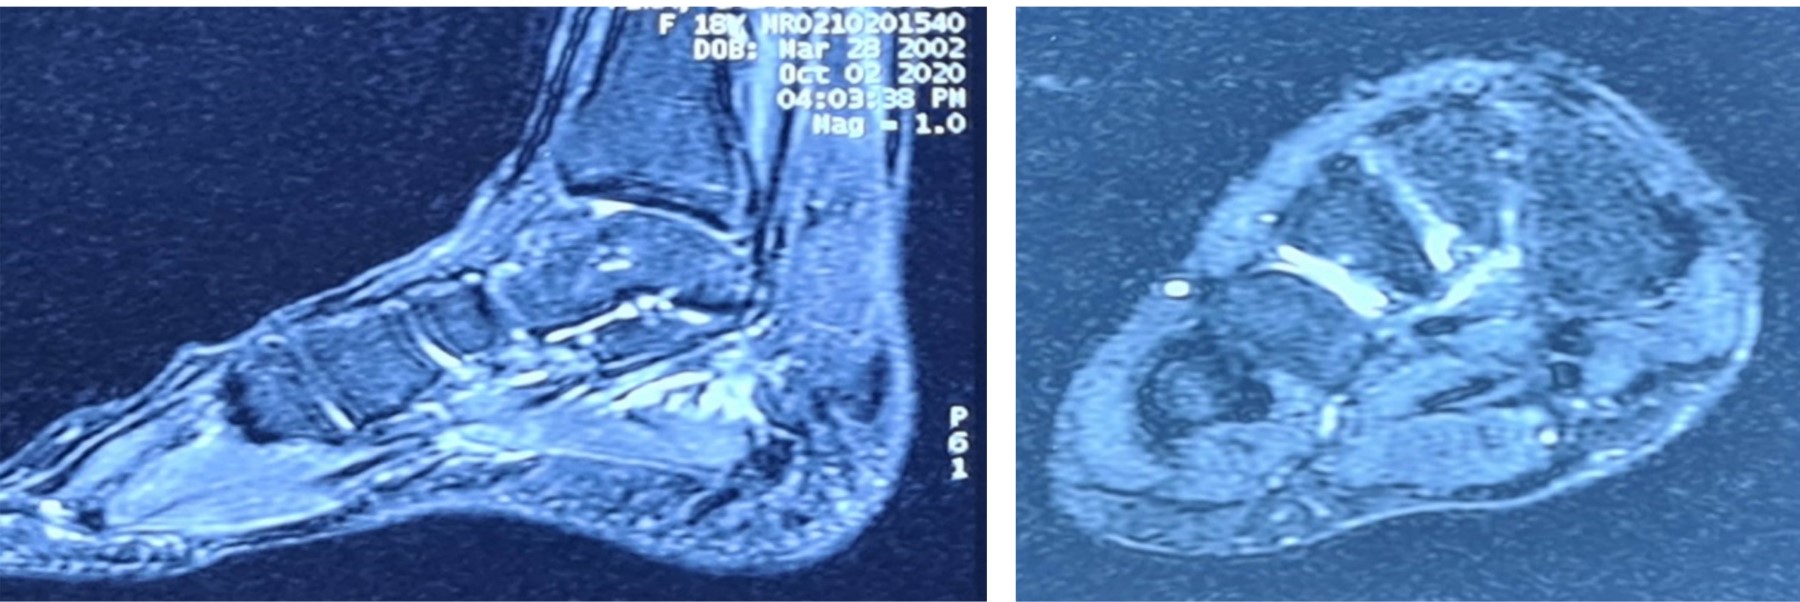

Se solicita entonces nueva RM, de la cual se informa: tenosinovitis del TP, FHL y del flexor común de los dedos (FD) así como aumento de líquido presente en espacio entre segundo y tercer cuneiformes (Figura 2).